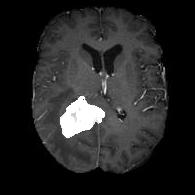

(a) (b) (c) (d)

Boundary Stream:

Fig. 2 demonstrates the output of each of the attention layers in our dedicated boundary stream. In essence, each attention layer progressively localizes the tumor and refines the boundaries. The first attention layer has learned rough estimate of the boundaries around the tumor and localized it, whereas the second and third layers have learned more fine-grained details of the edges and boundaries, refining the localization. Moreover, since our architecture leverages a dilated spatial pyramid pooling to merge the learned feature maps of the regular segmentation stream and the boundary stream, multiscale regional and boundary information have been preserved and fused properly, which has enabled our network to capture the small structural details of the tumor.

(a) (b) (c) (d) (e)

Comparison to Competing Methods:

We have compared the performance of our model against the most popular deep learning-based semantic segmentation networks, U-Net [9] and V-Net [7] (Fig. 3). Our model outperforms both by a considerable margin in all evaluation metrics. In particular, U-Net performs poorly in most cases due to the high false positive of its segmentation predictions, as well as the imprecision of its boundaries. The powerful residual block in the V-Net architecture seems to alleviate these issues to some extent, but V-Net also fails to produce high-quality boundary predictions. The emphasis of learning useful edge-related information during the training of our network appears to effectively regularize the network such that boundary accuracy is improved.